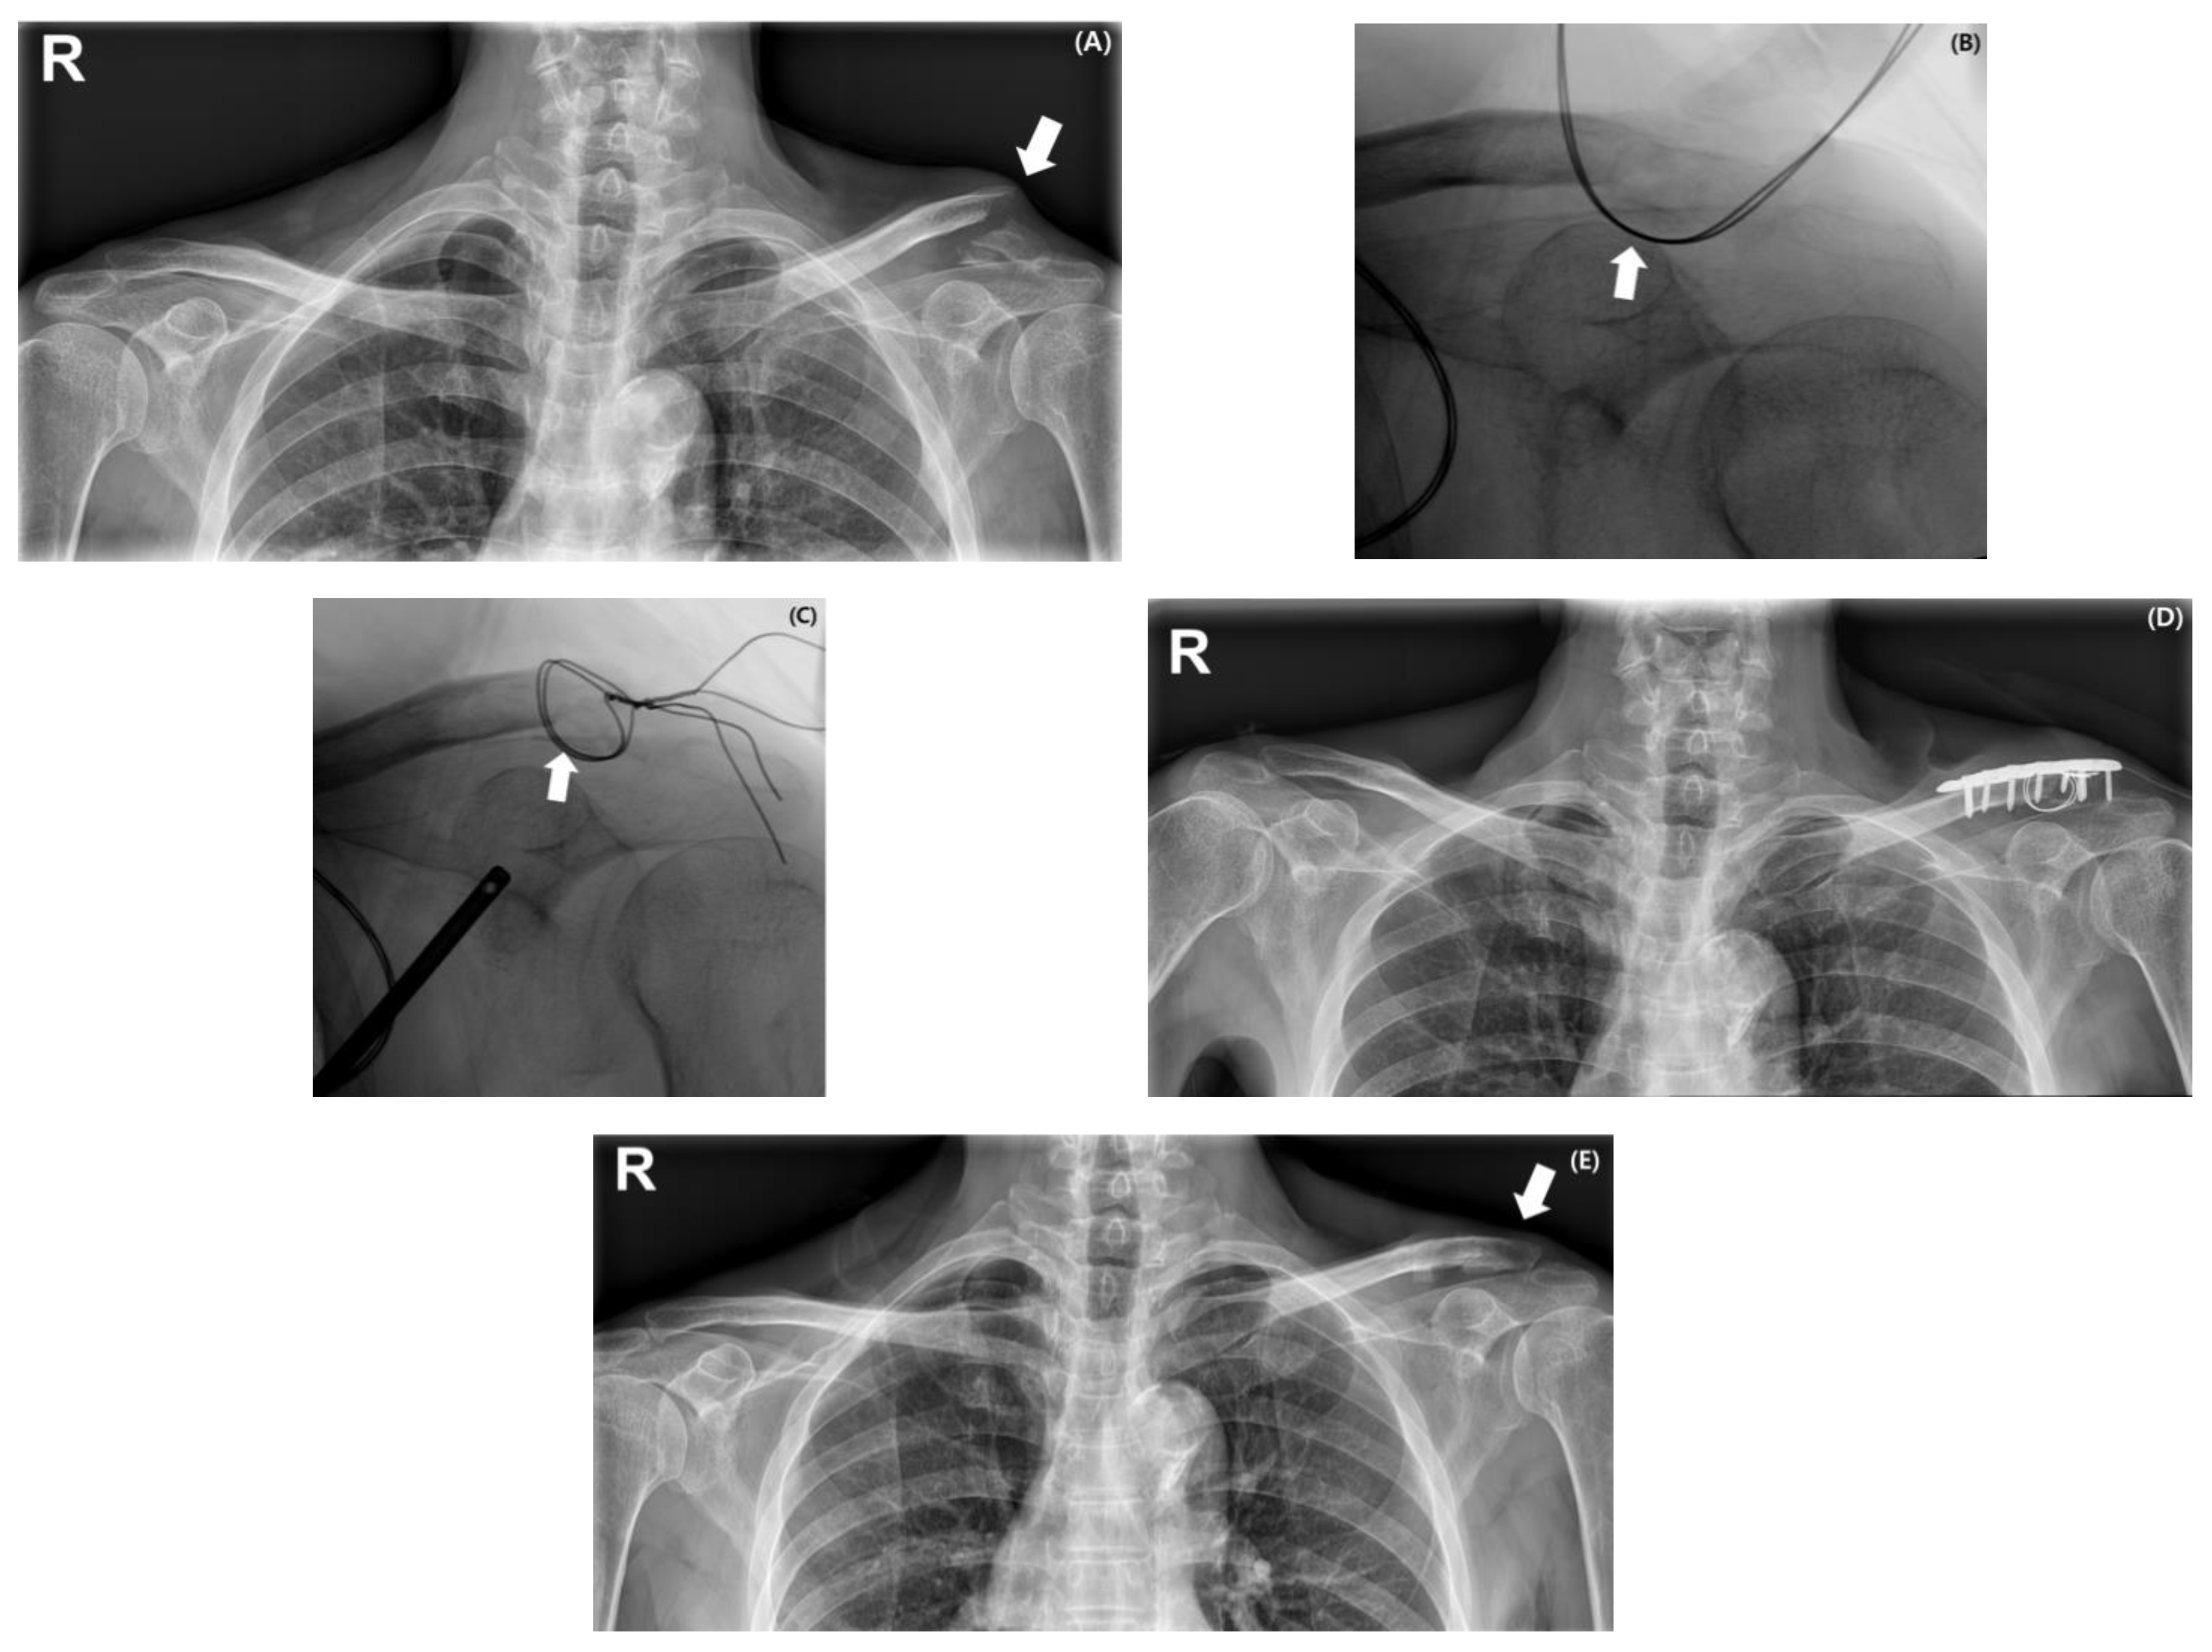

2.2. Surgical Procedures